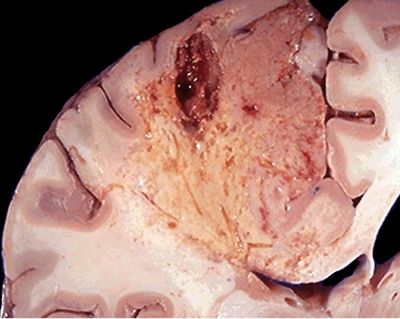

Se produce cuando hay una autolisis ¨Digestión enzimatica por parte de las lisosomas de las propias células muertas ¨

Image:

8e1e84fd-98bd-4111-accd-45ac44304aae (image/jpg)

Answer

Isquemia

Necrosis de licuefacción

Necrosis grasa